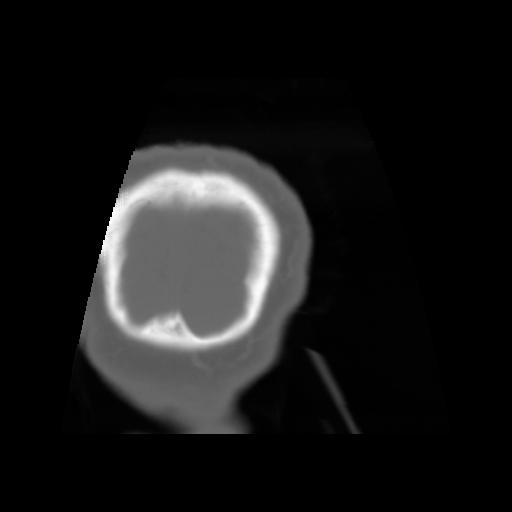

5 CEREBRO,,Coronal,3.000,CEREBRO,Coronal,